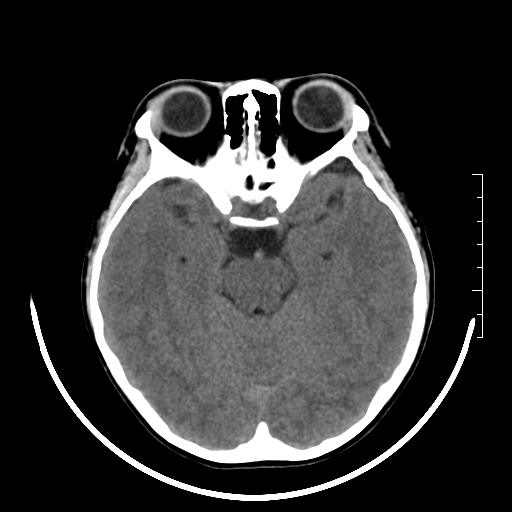

标题: PED3377:m、9y,恶心、呕吐,每月发作2-3次。 [打印本页]

标题: PED3377:m、9y,恶心、呕吐,每月发作2-3次。

颅脑ct轴位平扫颅内未见明确异常。

右侧基底节区见钙化灶

右侧壳核多枚点状钙化灶。去请结合临床。

右侧壳核多枚点状钙化灶,请结合临床。

右侧壳核多发钙化灶,请结合临床。